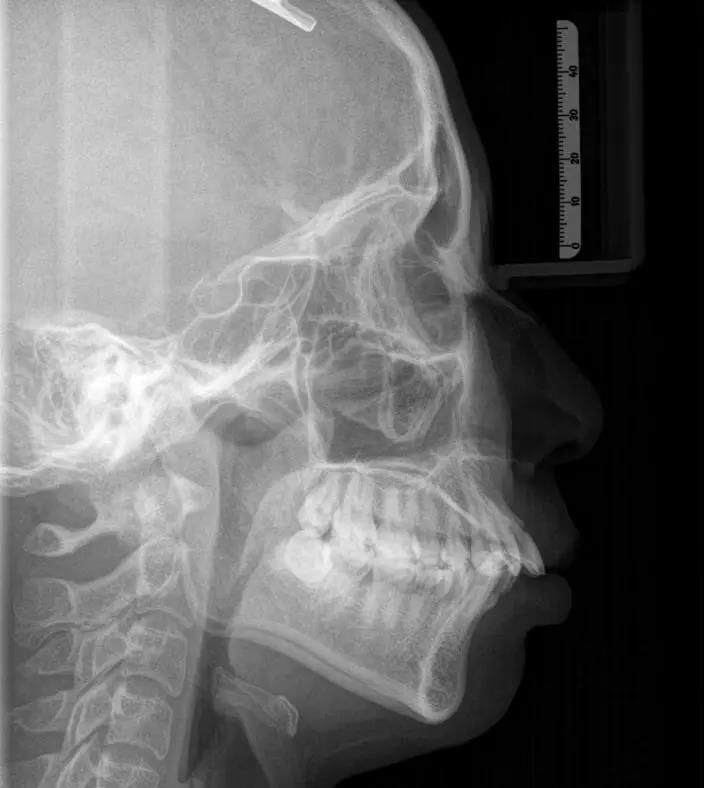

②头颅正侧拉片:这种牙片主要用于正畸,便于医生从正、侧角度观察牙齿情况。